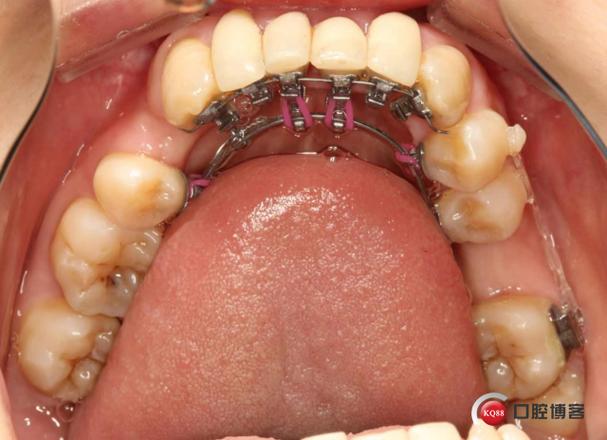

个性化托槽定制

方案确定后,技师根据数字牙模通过CAD/CAM系统设计托槽位置与形态,3D打印个性化托槽(每颗牙齿托槽独立设计,确保与舌侧牙面完全贴合),定制周期约2-4周。